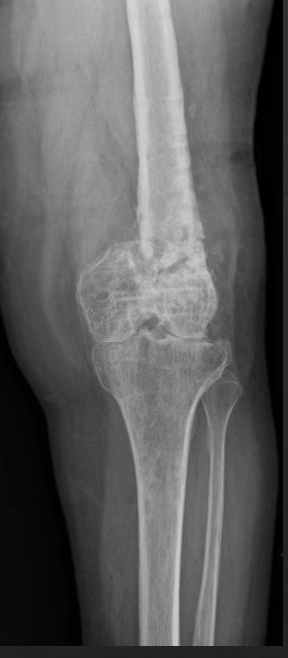

Q

Identify the complication seen by the radiograph

A

Distal femur fracture malunion